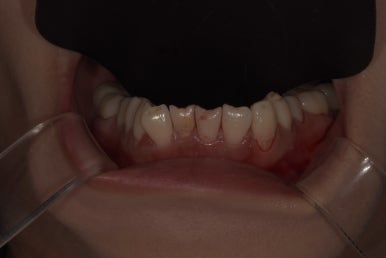

특히 오른쪽 아랫니(#42)는 치아가 기울면서 앞으로 튀어나와있어

이 치아를 다른 치아와 밸런스를 맞춰 배열을 고르게 만들고 싶어하셨는데요.

라미네이트, 올세라믹크라운 치료 전 하악 모습

2023-06-23

다른 치아는 모두 치아 앞 표면만 살짝 다듬어 라미네이트를 부착하는 방식으로 치료가 가능하지만,

#42 치아는 배열 개선을 위해 크라운 치료가 불가피해 해당 치아만 올세라믹크라운으로 치료 계획을 세웠습니다.

또한 해당 치아가 윗니와 닿지 않도록 교합을 정교하게 체크했고, 이갈이 장치도 함께 제작하기로 했습니다.

특히 오른쪽 아래 #42 치아는 기울어져 있던 치아가 반듯하게 개선되어 훨씬 고르게 변했고,

주변 치아와 조화가 잘 이루어지는 모습입니다.

라미네이트 치료 전후 상악, 하악 모습

(치료 전) 2023-06-23

(치료 후) 2023-07-05